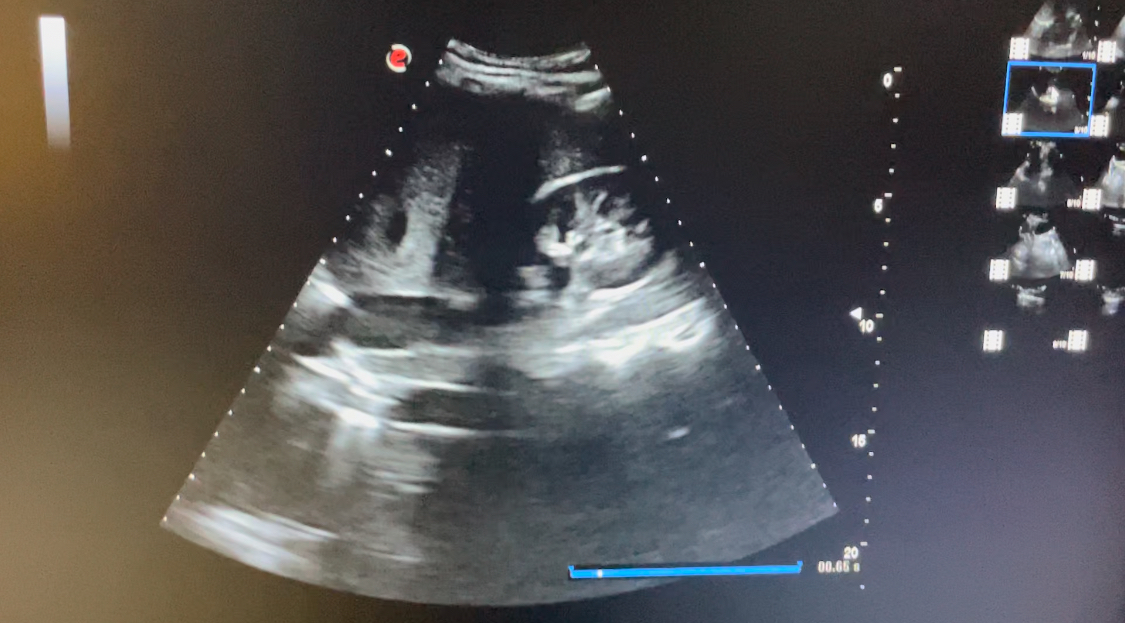

Estudio ecográfico con sonda abdominal de baja frecuencia, siguiendo protocolo ECO-FAST. Se explora región subxifoidea sin apreciarse presencia de líquido en saco pericárdico. Hipocondrio derecho libre de líquido en espacio de Morrison. Hipocondrio izquierdo sin presencia de líquido en espacio esplenorrenal. Imagen de región supra púbica, corte longitudinal y transversal donde no se observa líquido libre en saco de Douglas.